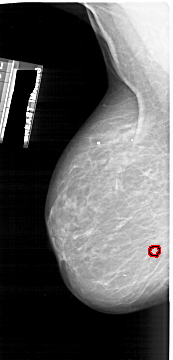

A_1866_1.LEFT_MLO

LEFT_MLO LINES 6466 PIXELS_PER_LINE 3106 BITS_PER_PIXEL 12 RESOLUTION 43.5 OVERLAY

FILE: A_1866_1.LEFT_MLO.OVERLAY

TOTAL_ABNORMALITIES 1

ABNORMALITY 1

LESION_TYPE CALCIFICATION TYPE PLEOMORPHIC DISTRIBUTION CLUSTERED

ASSESSMENT 4

SUBTLETY 4

PATHOLOGY BENIGN

TOTAL_OUTLINES 1

BOUNDARY